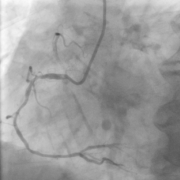

The proposed methods are evaluated on a coronary angiograms dataset consisting of 53 grayscale images sized at 400×400400400400\times 400 pixels with available ground truth for stenosis detection by an expert. The images are selected from CDs in DICOM format of 30 patient cases provided by Qilu Hospital (Qingdao).

To make a preliminary test on the effectiveness of our proposed solution, we selected three images with large differences in vessel structures for independent experiments and the results are shown in Fig. 6. As can be seen from the figures, even though the vessel structures are different, the whole algorithm in this paper still has a good experimental effect on each image. Next, we will give more detailed and quantitative results of our methods.